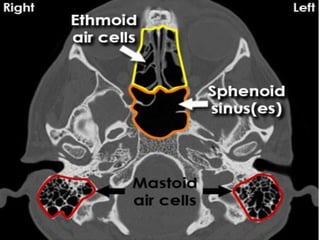

• Paranasal sinuses and mastiod are structures that

are hypodense in normal cases.

Disorders of Sinuses

• Acute bacterial sinusistis.

• Chronic purulent sinusitis.

• Fungal infection.

• Mucocoele.

• Tumors.

Left Mastiod disease

Rt mastiod disease

Right Mastioditis